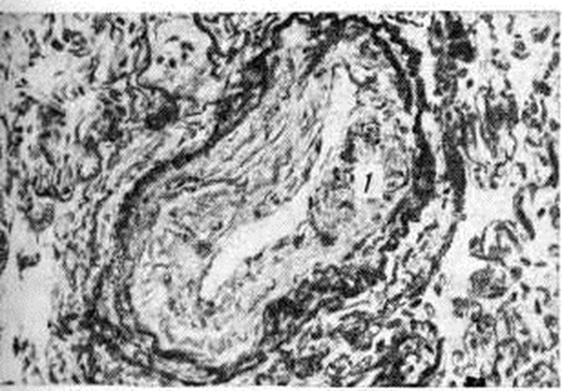

При посткапиллярной форме нарушение оттока из лёгочных вен приводит к гипертрофии мышечных элементов мелких вен лёгкого с последующим склерозом стенки, что вызывает сужение их просвета (рисунок 4). Это наиболее выражено в нижних долях лёгких. Мелкие ветви артерий терминальных и респираторных бронхиол суживаются вследствие гипертрофии средней оболочки (рисунок 5), иногда склероза внутренней оболочки, что является результатом их рефлекторного спазма. В мелких артериях отмечается миоэластоз с последующим фиброзом средней оболочки; капилляры дольше других отделов сосудистого русла лёгких остаются неизменёнными, лишь в стадии декомпенсации отмечается фиброз их стенки и появление сидерофагов (альвеолярные макрофаги, заполненные гемосидерином).